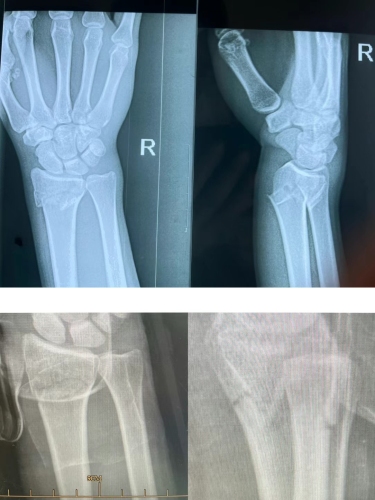

骨折脱位 颈肩腰腿痛 腱鞘炎 梨状肌综合征 腰肌劳损 筋膜炎 腕管综合征 肱骨外上髁炎 肱骨内上髁炎 神经性关节病 骨质疏松症 痛风 股骨头坏死 强直性脊柱炎 踝关节扭挫伤 关节脱位 扭伤 烫伤 桡骨远端骨折 滑膜炎

非手术治疗儿童/成人四肢骨折脱位之疾。 伤科理筋手法治疗各类因滑雪、球类等各类运动造成的急性损伤。

外籍友人在深圳最大室内滑雪摔伤致桡骨远端骨折 展开>